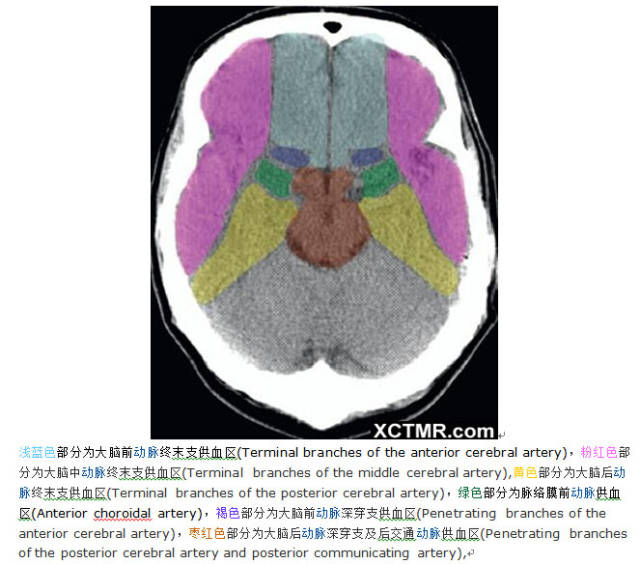

颅脑ct彩色解剖

图片尺寸640x564